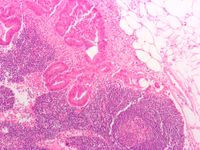

- 림프절 생검: 림프절 조직을 채취하여 현미경으로 검사하여 림프절 비대의 정확한 원인을 진단한다.[23]

국소 암은 종양 세포가 림프절로 전이되어 림프절을 비대하게 만들 수 있다. 림프절 침범은 암 진단, 치료, 병기 설정에 중요한 영향을 미친다.[30] 암에 대한 검사 일환으로 림프절을 영상화하거나 외과적으로 제거할 수 있다. 제거된 림프절은 병리학 전문의가 현미경으로 검사하여 암세포(림프절로 전이된 세포) 증거가 있는지 확인한다. 암 병기, 치료, 예후는 림프절 전이 여부에 따라 달라진다.